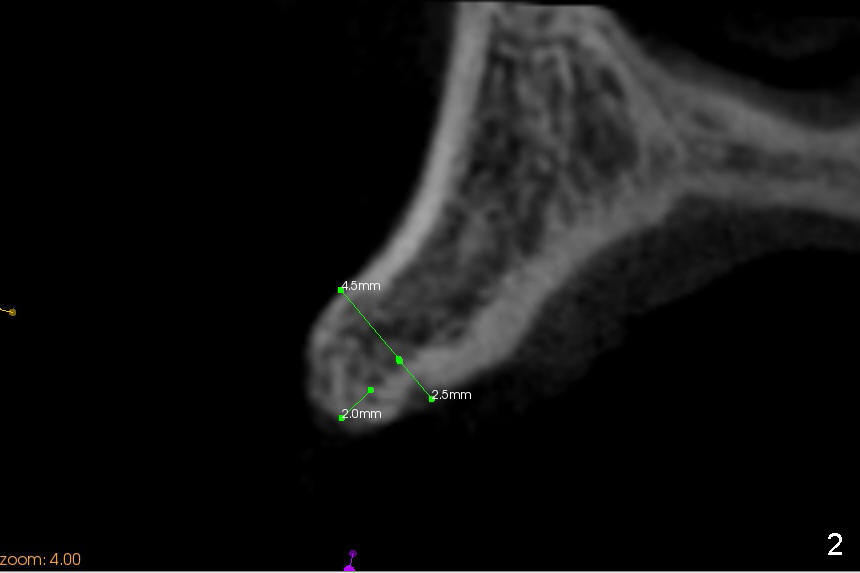

A 45-year-old lady has history of chronic periodontitis. The tooth #6 has lost several years (Fig.1). The buccolingual width decreases (Fig.2 (7mm), as compared to #11 in Fig.6 (10 mm)). Bone expansion is necessary for implantation. It should be done gently, since she is a dental phobic. First the crestal cortex is split with a surgical fissural bur (Fig.3 red line), followed by thin osteotomes (Fig.4 green line: scalpel, bone scalpels (probably until 5 or 6 mm, as indicated by Fig.1 (mesiodistal width)), bone blades (until 5.5 mm)). If the patient cannot tolerate tapping, 1.6 mm pilot drill is used at the depth of 14 mm, followed by bone expanders (probably until 2.9/3.8 using handpiece). As expanders or rounded osteotomes increases in diameter (Fig.5 green arrow), the buccal plate moves buccally (pink arrow). The bone expansion improves cosmetics as well. The implant is planned to be 4.5x14 mm, bone level. Angled abutment is expected. In contrast, immediate implant prevents buccal plate atrophy and avoids bone expansion. How is the surgery?